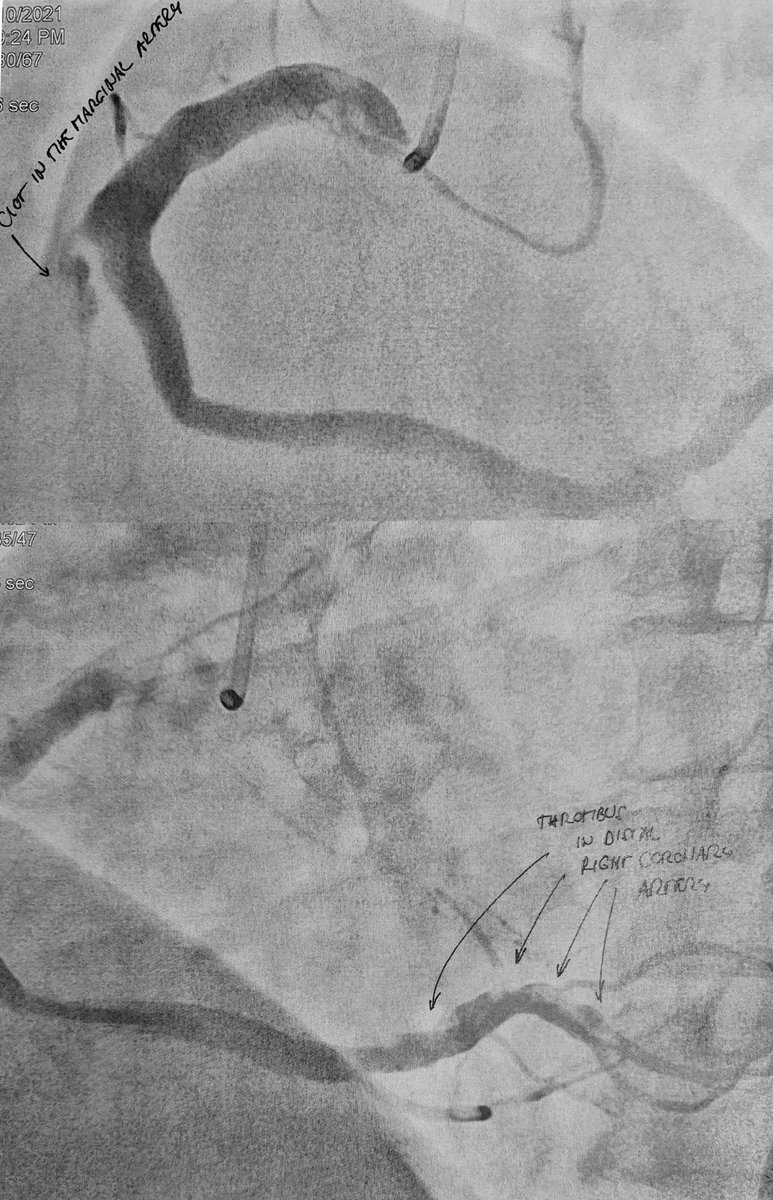

POST-VACCINE "COINCIDENCES" Case 1 →Johnson&Johnson Vaccine 2 weeks ago →Admitted with acute heart attack (inferior STEMI) →Right heart artery has multiple clots but no underlying narrowing or ruptured cholesterol plaque Conclusion: Vaccine-induced heart attack

POST-VACCINE "COINCIDENCES"

Case 1

→Johnson&Johnson Vaccine 2 weeks ago

→Admitted with acute heart attack (inferior STEMI)

→Right heart artery has multiple clots but no

underlying narrowing or ruptured cholesterol

plaque

Conclusion:

Vaccine-induced heart attack